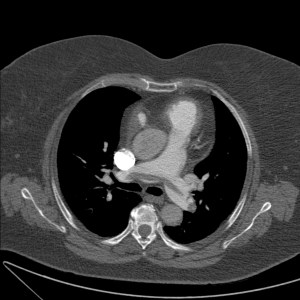

Cono de la pulmonar de calibre aumentado.

Cono de la pulmonar de calibre aumentado, indicativo de hipertensión pulmonar radiológica.